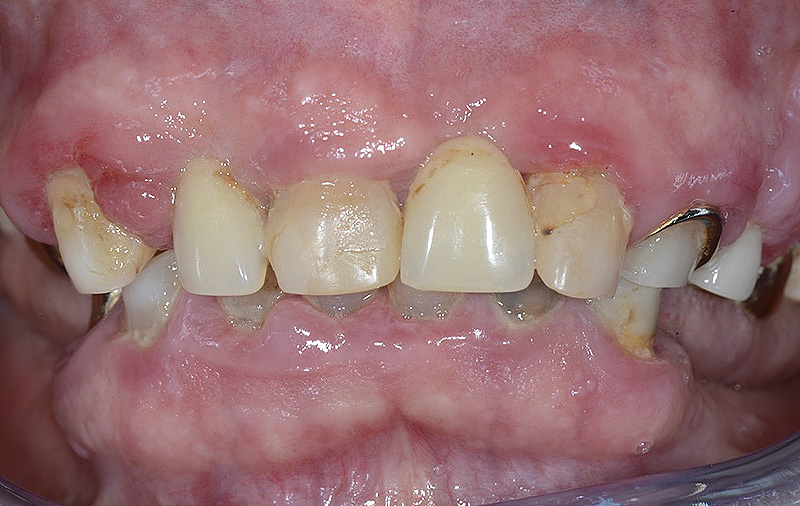

Vengono utilizzati 2 tipi di provvisori: il primo, cementato ai denti vicini, viene utilizzato dal momento dell’estrazione del dente fino ad impianto osteointegrato (circa 6 mesi); il secondo, avvitato direttamente all’impianto, ha una funzione di prova estetica ma soprattutto di guida per la maturazione dei tessuti gengivali peri-implantari portandoli verso la maturazione completa prima di posizionare la corona finale in disilicato di litio.